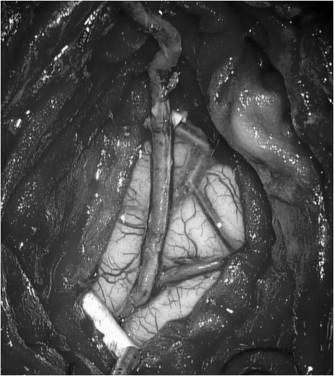

外六科吴杰主任、闫学强主治医生对患者进行了综合评估:患者3个月前为左侧脑室出血,且目前左侧半球供血不足比右侧显著,医生拟先实施左侧脑内血管重建术,二期实施右侧脑内血管重建术。几日后,患者在全麻下接受左侧颞浅动脉-大脑中动脉搭桥术,医生采取左侧额颞直切口,长约175px,创伤小(术中如图4);术中医生利用荧光造影,可清晰见到吻合血管通畅(如图5)。整个手术过程顺利,患者术后恢复良好,复查DSA,吻合血管通畅,颅内血供明显改善(如图6),并无神经功能缺失。目前患者已痊愈出院。

图4,术中左侧颞浅动脉与大脑中动脉进行血管吻合